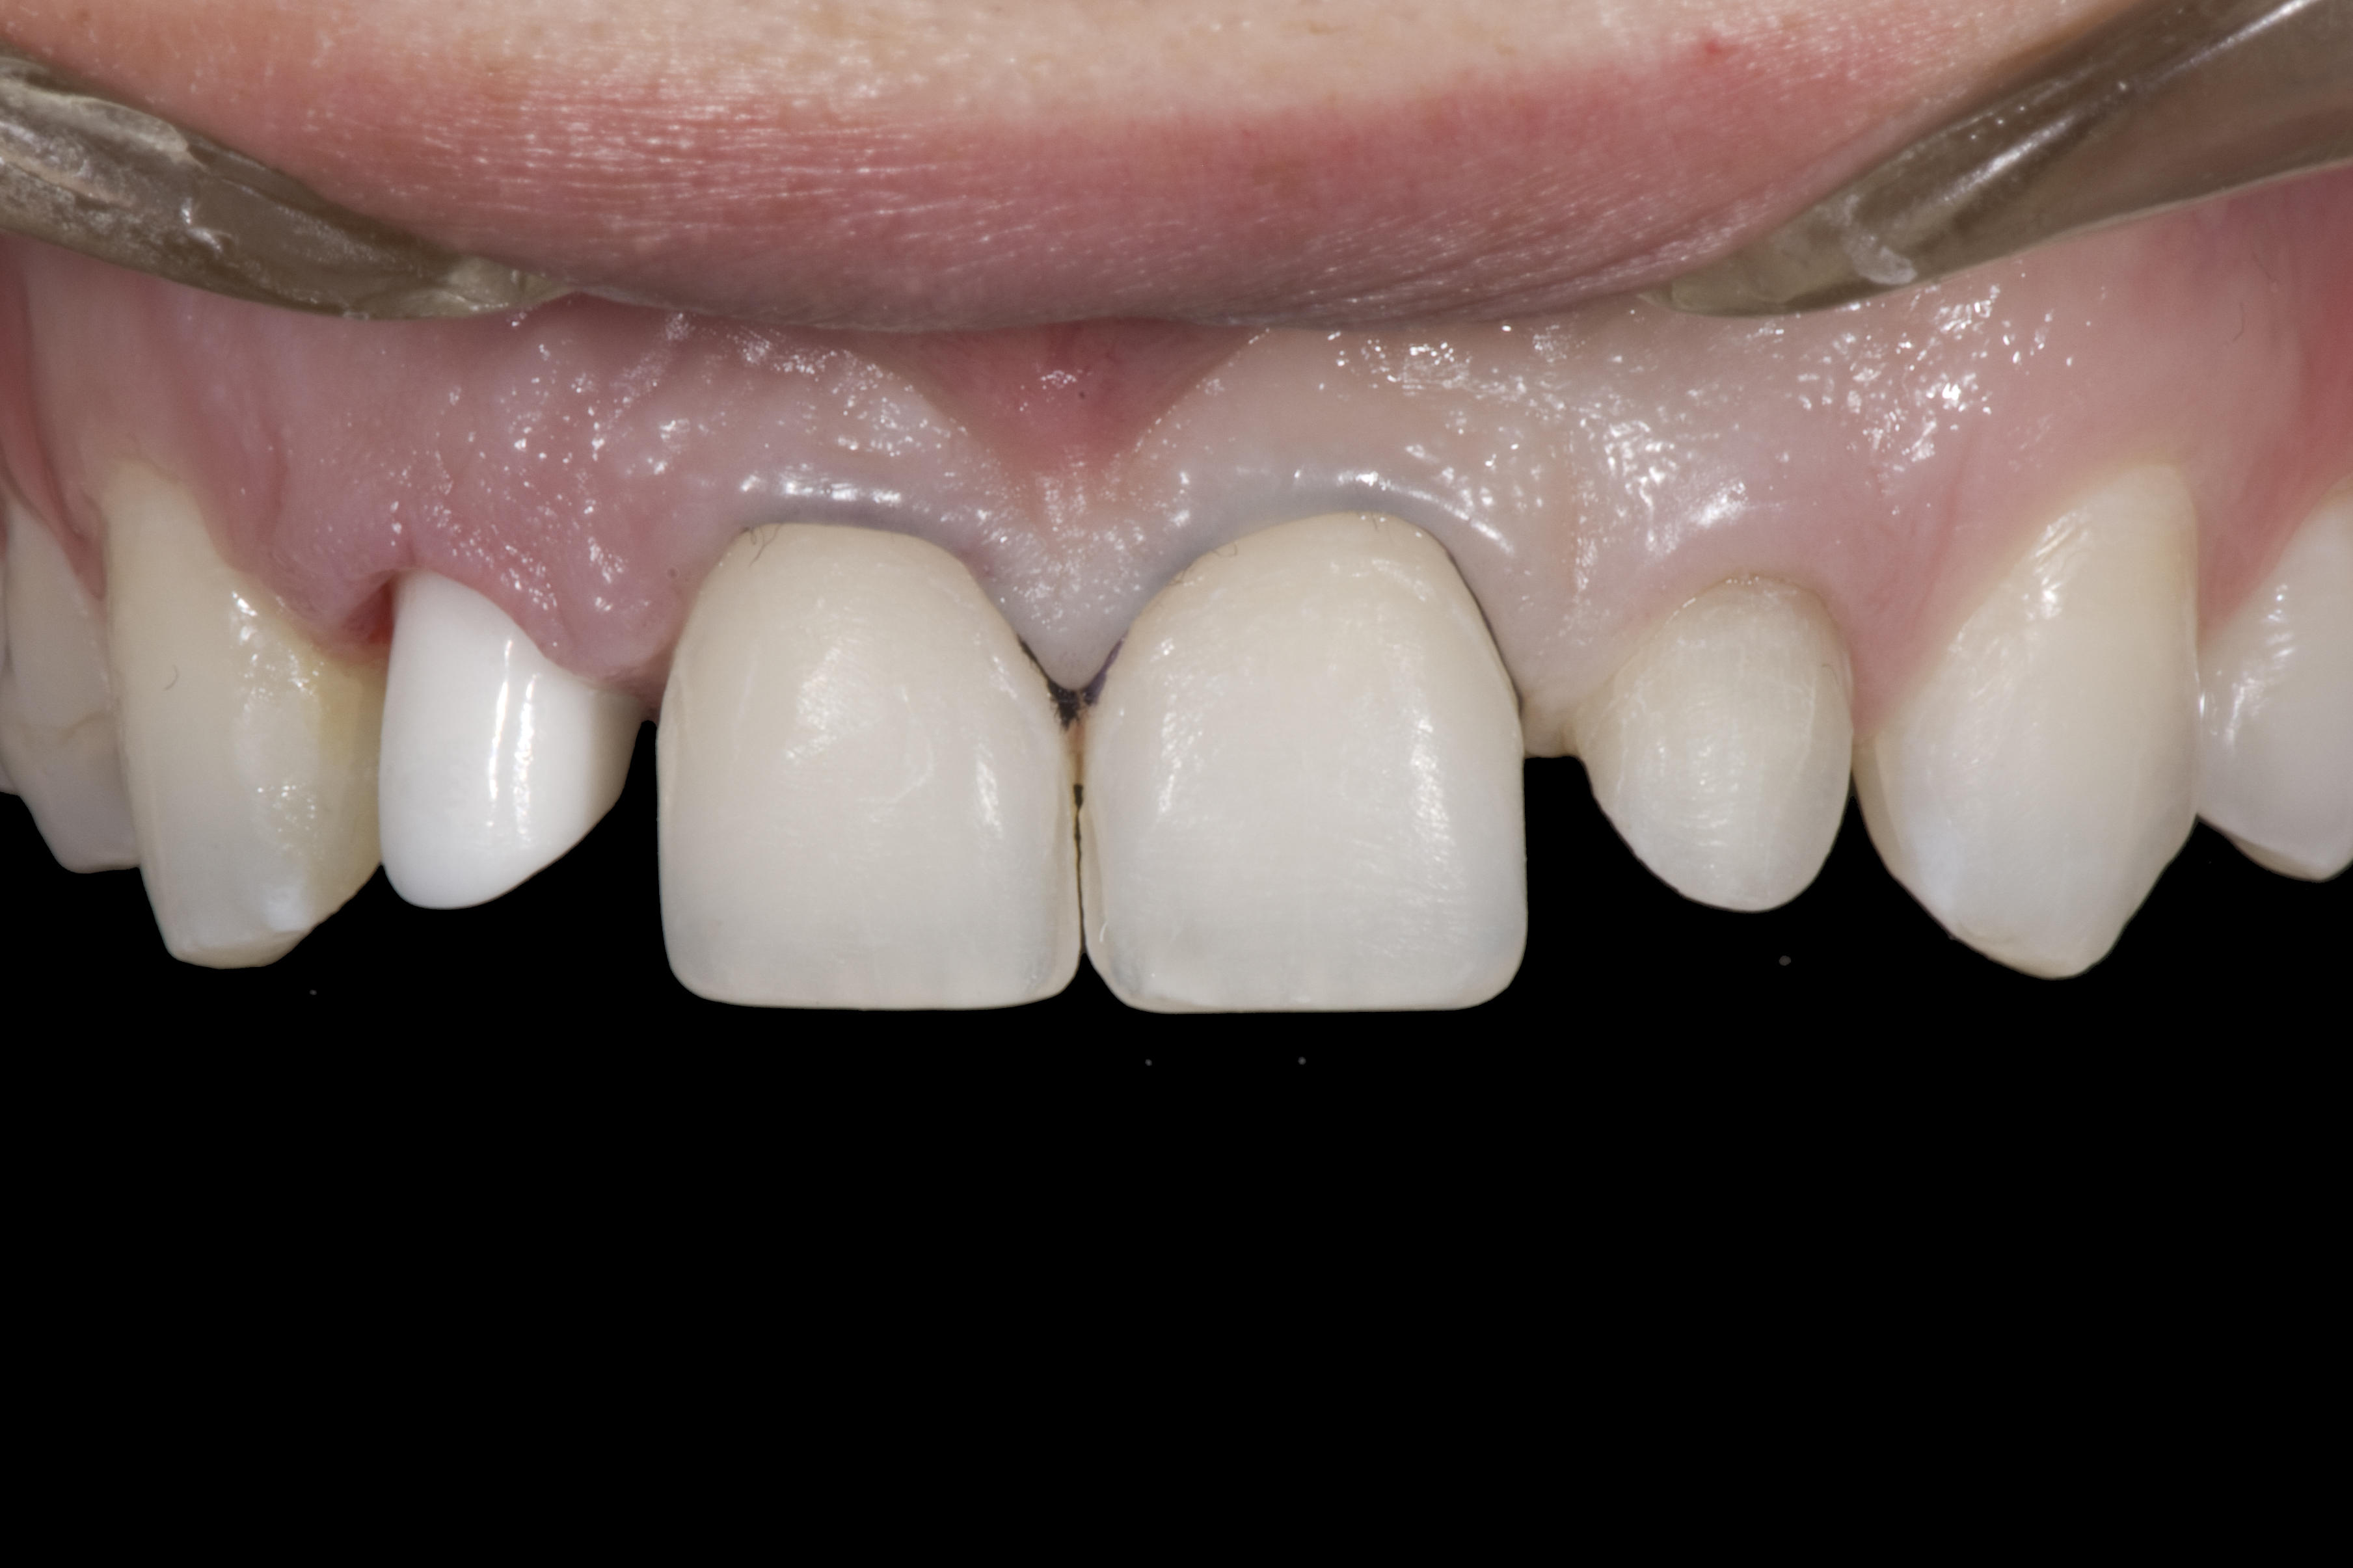

(3.) After resin-based composite bonding of the three incisors.

Figure 3